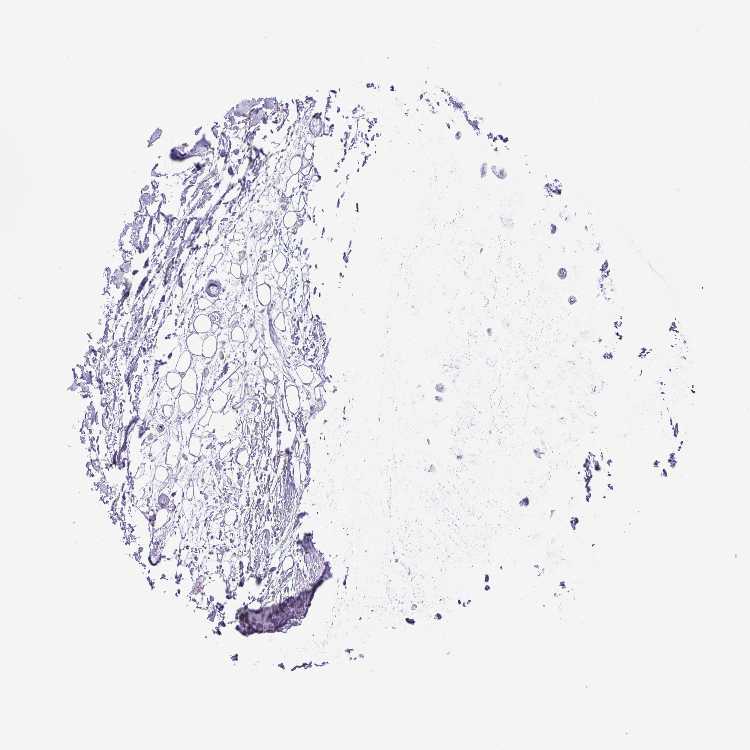

SOFT TISSUE 2 - Antibody stainingi

Antibody staining in the annotated cell types in the current human tissue is reported as not detected, low, medium, or high, based on conventional immunohistochemistry profiling in selected tissues. This score is based on the combination of the staining intensity and fraction of stained cells.

Each image is clickable and will lead to virtual microscopy that enables deeper exploration of all samples and also displays staining intensity scores, fraction scores and subcellular localization as well as patient and tissue information for each sample.

Antibody HPA049905

Fibroblasts High

Peripheral nerve Not detected